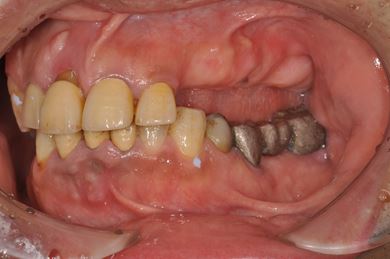

インプラント治療+セラミック治療+歯周組織再生療法

| 性別/年齢 | 男性 / 52歳 | ||||||||||||||||||||||||||||||||

| 主訴 | 歯を徹底的に治したい。 | ||||||||||||||||||||||||||||||||

| 治療方針 | インプラント、セラミック治療にて、機能的・審美的回復を行う。 | ||||||||||||||||||||||||||||||||

| 治療内容 | インプラント10本(テンポラリーインプラント2本)、メタルボンドセラミッククラウン6本(メタルボンド用土台3本)、ハイブリッドセラミッククラウン14本(ハイブリッドセラミック用土台1本)、歯肉歯槽骨整形術、結合組織移植術 | ||||||||||||||||||||||||||||||||

| 総治療費 | 5,206,343円 | ||||||||||||||||||||||||||||||||

| 治療期間 | 1年6ヶ月 |